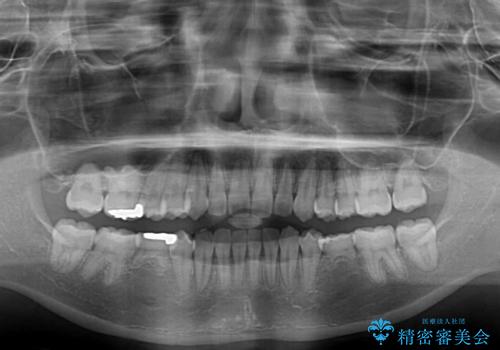

- 犬歯のクロスバイトを気にして来院された患者様です。

マウスピース矯正とワイヤー矯正の両方を提案しましたが、インビザラインの自己管理が煩わしいとのことで、ワイヤー装置による矯正治療を行うこととしました。

犬歯は歯根が太くて長いため、クロスバイトを改善するのは大変であることが多いですが、比較的スムーズに改善することができました。

インビザラインであったら、もっと期間はかかっていたような印象です。